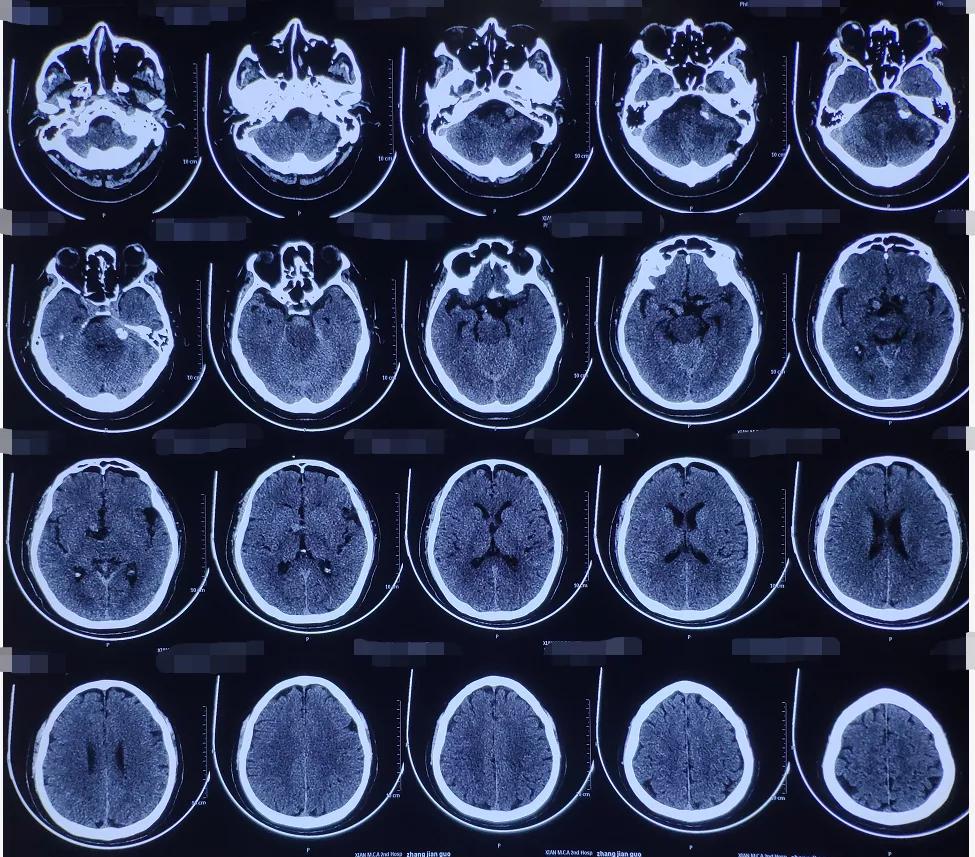

术后影像学资料:

术后,患者恢复很好,不适症状全部消失,且无并发症。